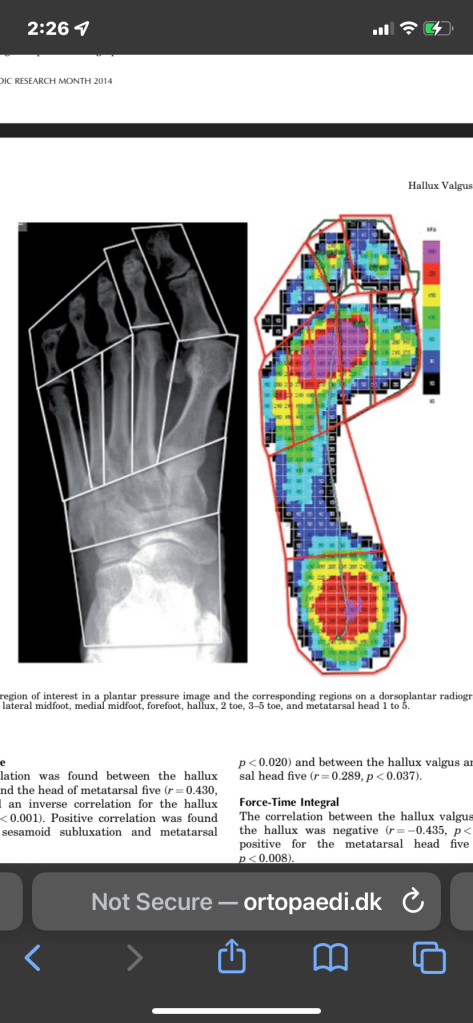

Finally the big toe is very important for your structure. Keep this in mind and make sure to wear shoes with a wide toebox. The big toe is our most important toe, but it is also the one that is most injured and deformed by modern shoes. You may have to buy different shoes, but these are becoming more common. Most modern shoes crush the feet and ruin our mobility. I provide some more info and links below.